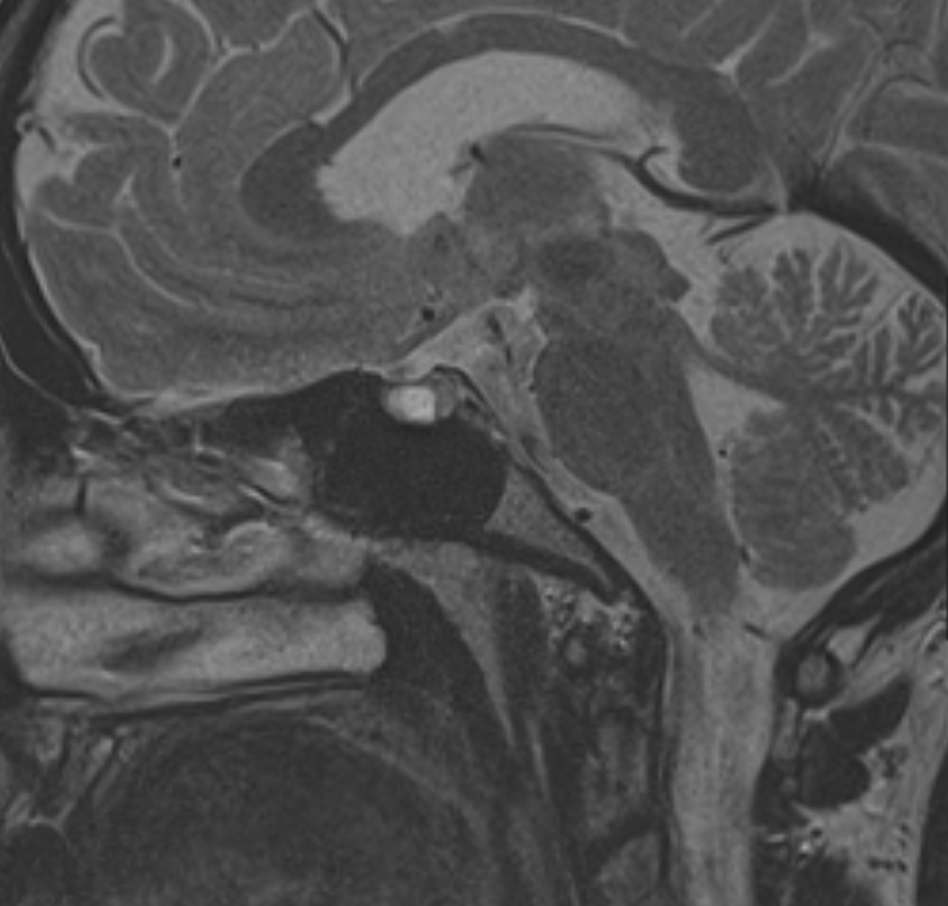

МРТ головного мозга позволяет оценить состояние всех структур головного мозга, однако для выявления патологии гипофиза назначается дополнительно МРТ гипофиза с прицельным осмотром области турецкого седла. Это два разных обследования, каждое из которых имеет свой протокол сканирования. Причем в подавляющем большинстве случаев МРТ гипофиза проводится с контрастным усилением, так как без этого данное исследование малоинформативно.

Опухоли гипофиза являются достаточно часто встречающейся патологией, особенно у людей молодого и среднего возраста. При этом выявляются как злокачественные, так и доброкачественные новообразования. В большинстве случаев обнаруживаются аденомы гипофиза (доброкачественные образования). При проведении стандартной МРТ головного мозга можно выявить достаточно большие опухоли гипофиза (от 1 см), а для выявления опухолевых образований меньших размеров (микроаденом) требуется МРТ гипофиза с контрастным усилением.

Метод позволяет создавать детализированные изображения всех структур головного мозга, в том числе области турецкого седла, и по праву считается лучшим способом диагностики любых объемных образований гипофиза. С помощью МРТ головного мозга и гипофиза можно выявить макроаденомы и большинство микроаденом (размером до 3мм).